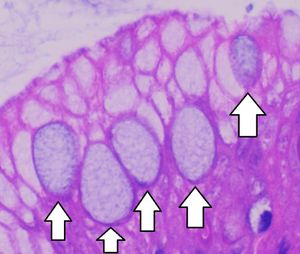

바렛 식도의 진단에는 내시경 검사와 현미경을 통한 조직학적 확인이 모두 필요하다. 특히, 장(腸) 형성이상이라고 불리는 술잔 세포의 존재가 필수적이다.[21]

바렛 식도를 확진하려면 술잔 세포의 존재, 즉 장 형성이상이 필수적이다. 술잔 세포는 다른 형성이상 원주 세포와 함께 나타나는 경우도 많지만, 진단을 위해서는 반드시 존재해야 한다. 형성이상은 내시경으로 확인할 수 있지만, 세포의 성격(위 또는 결장)을 확인하려면 생검 표본을 현미경으로 검사해야 한다. 결장 형성이상은 상피에서 술잔 세포를 확인하여 감별하며, 정확한 진단을 위해 필수적이다.[21]

정상 식도 점막하선 관의 이행 상피에서 발생하는 술잔 세포나 "가성 술잔 세포" 등 바렛 식도와 유사한 조직학적 소견이 많다. Alcian blue pH 2.5 조직화학 염색은 진정한 장형 점액과 유사 소견을 감별하는 데 사용된다. 최근에는 CDX-2 항체를 이용한 면역조직화학 분석으로 진정한 장 형성이상 세포를 확인하기도 한다. AGR2 단백질은 바렛 식도에서 발현이 증가하며,[22] 바렛 상피와 정상 식도 상피를 구별하는 생체표지자로 활용될 수 있다.[23]

바렛 식도는 정상 식도 점막하선 관의 이행 상피에서 발생하는 술잔 세포나 "가성 술잔 세포" 등과 같이 유사한 조직학적 소견을 보이는 경우가 많으므로, 감별 진단이 중요하다. Alcian blue pH 2.5 조직화학 염색이나 CDX-2 항체를 이용한 면역조직화학 분석을 통해 진정한 장 형성이상 세포를 확인할 수 있다. AGR2 단백질은 바렛 식도에서 발현이 증가하며,[22] 바렛 상피와 정상 식도 상피를 구별하는 생체표지자로 사용할 수 있다.[23]